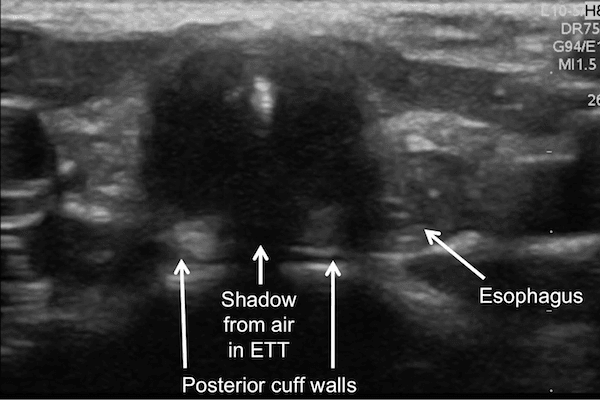

If the cuff is not seen, sweep the probe superiorly along the trachea to the level of the vocal cords to search for the saline-inflated cuff. Once air bubbles have dissolved, the saline inflated cuff is recognized by its posterior wall, appearing as horizontal hyperechoic lines interrupted by shadowing from air within the endotracheal tube.